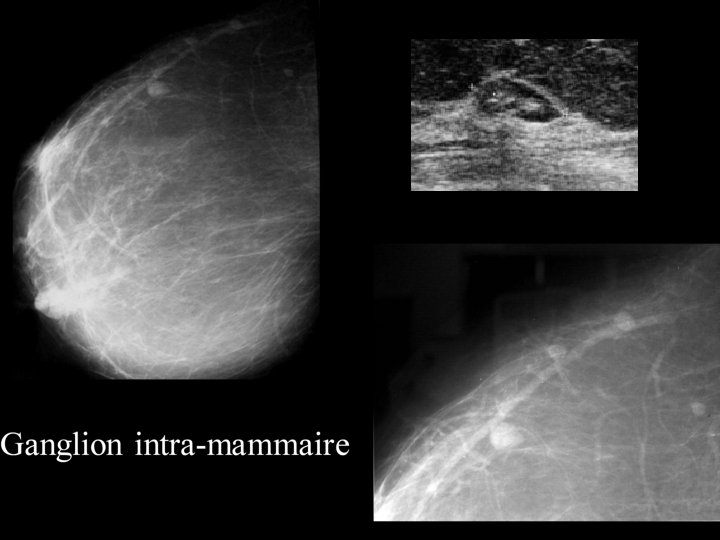

LESIONS BENIGNES RARES Tumeurs myoépithéliales Tumeurs amyloïdes Adénome lactant Papillomatose juvénile Lésions frontières: cicatrice radiaire Angiomes Mastopathie fibreuse associée au diabète Ganglion intramammaire

Ganglion intra-mammaire: • Très fréquent • MAMMOGRAPHIE: ▫ Opacité ovalaire bien limitée ▫ siège à la partie basse du prolongement axillaire ▫ avec centre ou encoche latérale transparente • ECHOGRAPHIE: ▫ Nodule hypoéchogène homogène à centre hyper échogène